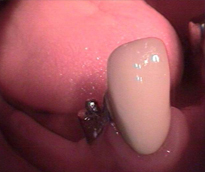

Endodonti (Kanal tedavileri,fiber post uygulamaları)